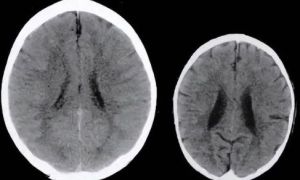

Cha mẹ sốc khi xem ảnh chụp não đứa trẻ 3 tuổi hay bị la mắng, tiến sĩ Harvard...

Cha mẹ sốc khi xem ảnh chụp não đứa trẻ 3 tuổi hay bị la mắng, tiến sĩ Harvard chỉ ra hệ lụy tiêu cực khi kỷ luật trẻ bằng lời nói

Cha mẹ luôn nghĩ rằng, việc la mắng con cái là cách để giáo dục một đứa trẻ trở nên ngoan ngoãn hơn. Thế nhưng, họ không ngờ rằng, hành động này có thể gây ra những tác động tiêu cực lâu dài tới một...